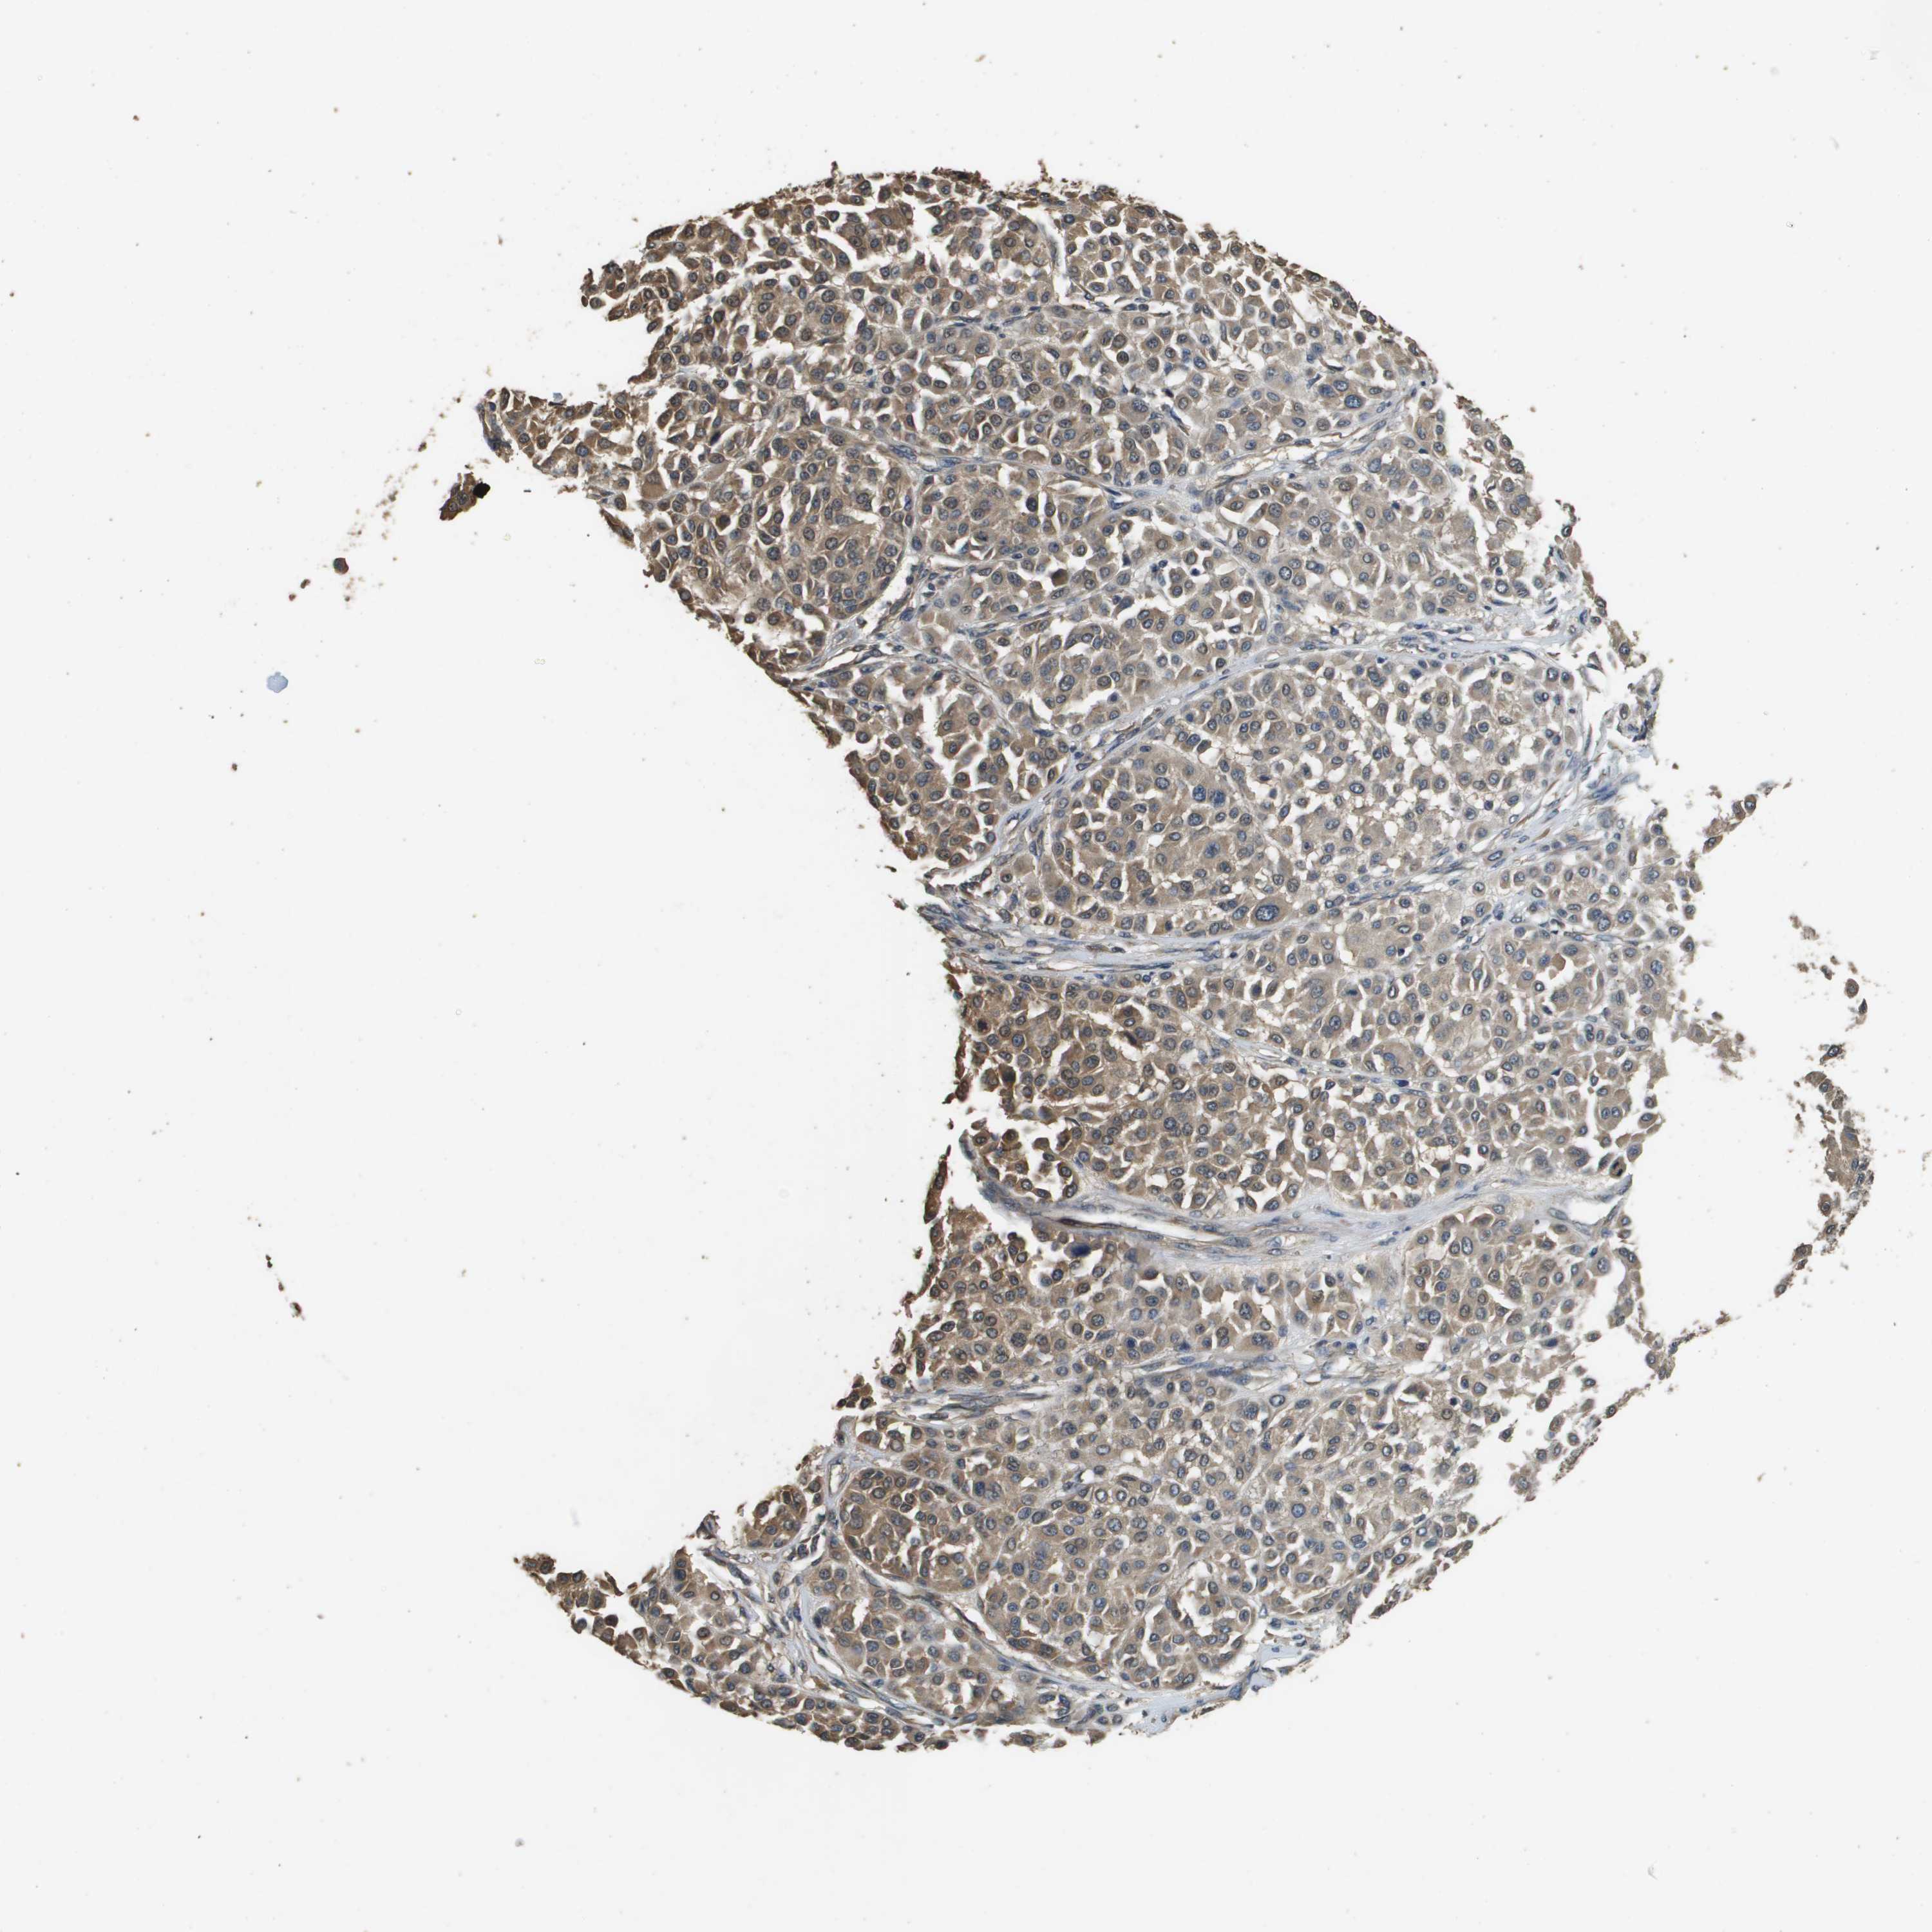

MELANOMA - Protein expressioni

A mouse-over function shows sample information and annotation data. Click on an image to view it in a full screen mode. Samples can be filtered based on level of antibody staining by selecting one or several of the following categories: high, medium, low and not detected. The assay and annotation is described here.

Note that samples used for immunohistochemistry by the Human Protein Atlas do not correspond to samples in the TCGA dataset.

Antibody stainingi

Antibody staining in the annotated cell types in the current human tissue is reported as not detected, low, medium, or high, based on conventional immunohistochemistry profiling in selected tissues. This score is based on the combination of the staining intensity and fraction of stained cells.

Each image is clickable and will lead to virtual microscopy that enables deeper exploration of all samples and also displays staining intensity scores, fraction scores and subcellular localization as well as patient and tissue information for each sample.

Antibody HPA059131

Antibody CAB017713

Staining

High

Medium

Low

Not detected

Intensity

Strong

Moderate

Weak

Negative

Quantity

>75%

75%-25%

<25%

None

Location

Nuclear

Cytoplasmic/membranous

Cytoplasmic/membranous,nuclear

Malignant melanoma, NOS

Malignant melanoma, Metastatic site